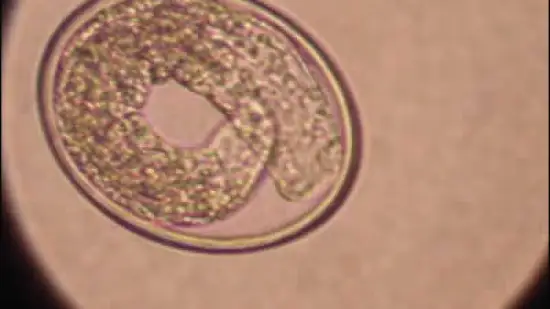

Cet œuf de parasite est celui :